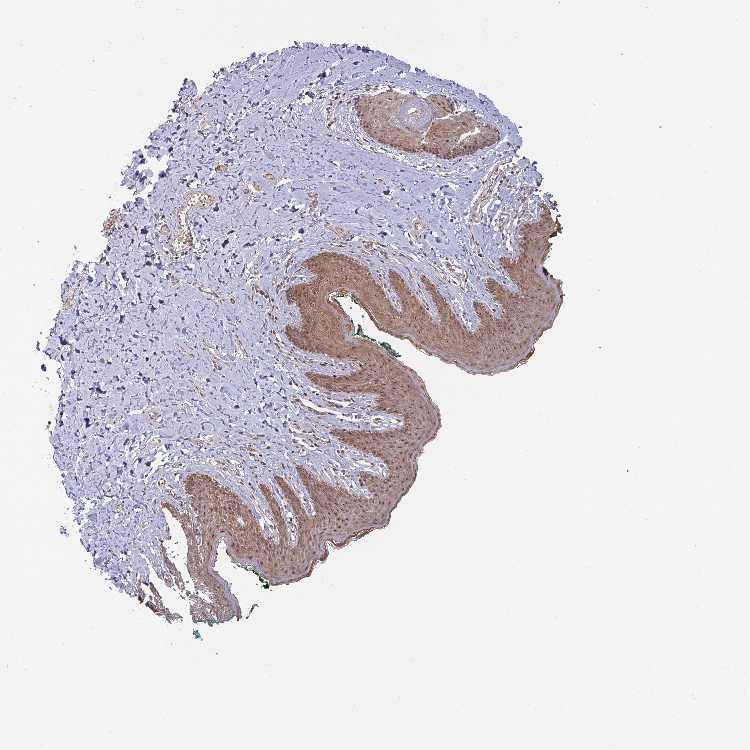

SKIN 2 - Antibody stainingi

Antibody staining in the annotated cell types in the current human tissue is reported as not detected, low, medium, or high, based on conventional immunohistochemistry profiling in selected tissues. This score is based on the combination of the staining intensity and fraction of stained cells.

Each image is clickable and will lead to virtual microscopy that enables deeper exploration of all samples and also displays staining intensity scores, fraction scores and subcellular localization as well as patient and tissue information for each sample.

Antibody HPA060459

Epidermal cells Medium